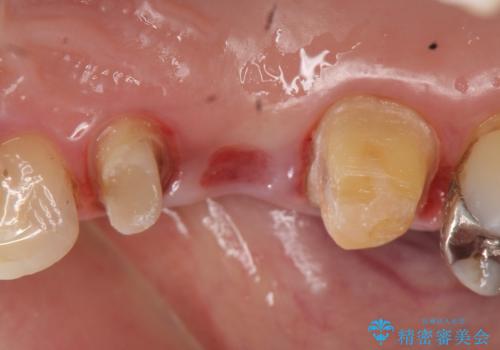

オールセラミッククラウン 歯根破折→抜歯→ブリッジ

- 右上の奥歯でものを咬むと痛むので診て欲しいといらっしゃった方の症例です。

診査の結果、歯根が破折しており保存不可能だったため抜歯し、ブリッジによる補綴を行いました。